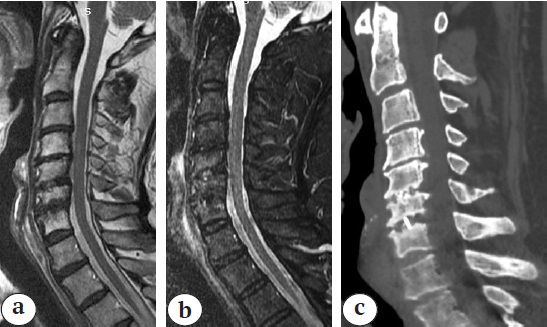

X-rays of the cervical spine at the time of discharge from the hospital and CT scans 10 months after the surgery are presented in Figure 5.

Fig. 5 (a, b, c, d). Sagittal (a) and frontal (b) X–rays, sagittal CT (c) 10 months after surgery: posterior transpedicular screw fixation correct position, solid anterior fusion C3–C7 formation detected. (d) - Axial (d) CT: posterior transpedicular screw fication correct position, solid anterior fusion C3–C7 formation detected

Postoperative period was uneventful, wounds healed by primary intention. Drains were removed on the 2nd day, patient was verticalized in a cervical brace on the 3rd day after the surgery. The intensity of vertebrogenic pain syndrome 10 months later was 2 points according to VAS, radicular pain syndrome in the upper extremities subsided, ODI – 15%, NDI – 14%. The value of correction of kyphotic deformity of the cervical spine was 46° according to Cobb.